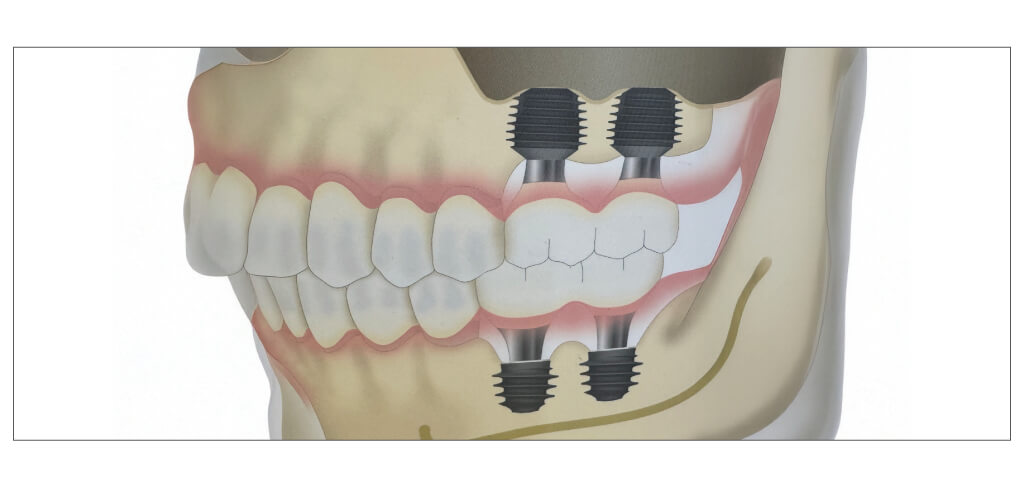

インプラント手術後

計画通りに上顎はオールオン4ザイゴマインプラント、下顎はオールオン4による手術を行いました。

さらに上顎の右側にテリゴイドインプラント、左側にワイド・ショートインプラントを追加することで安定性が高まりました。

上顎右側後方に埋入したザイゴマインプラントとテリゴイドインプラント。

上顎左側後方に埋入したザイゴマインプラントとワイド・ショートインプラント。

このインプラントのおかげで当日に仮歯を装着することができ、これから好きなものを美味しく食べられるようになります。